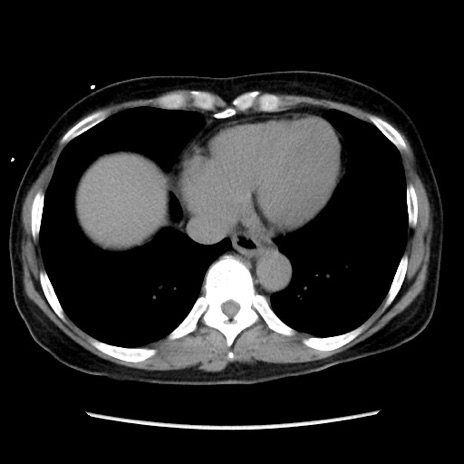

症例10(横断像)

【症例】 50歳代女性

【主訴】 腹痛

【現病歴】前日生レバーを食べた。今朝に排便あり。 昼前に突然発症の腹痛を生じ、当院救急外来を受診した。

【既往歴】 子宮筋腫にてで子宮全摘後

【身体所見】 意識清明、腹部:平坦、軟、下腹部やや左を中心に圧痛・反跳痛あり、筋性防御あり

【データ】WBC 7800、CRP 0.07